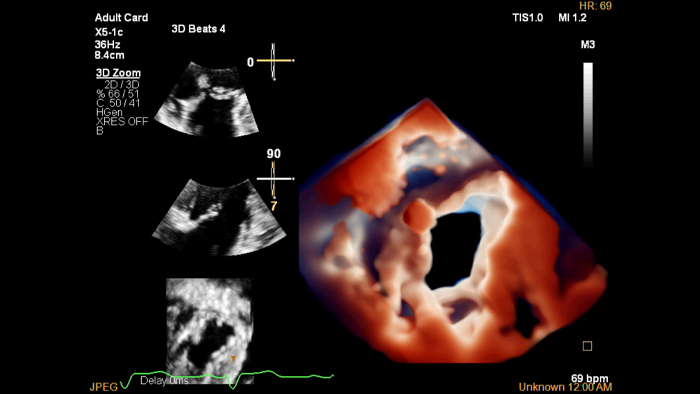

Imágenes realistas en ecocardiografía 3D

Una fuente de luz virtual resalta las estructuras y facilita la percepción de profundidad para una mejor interpretación de las imágenes de enfermedades cardiovasculares.

Prof. José Luis Zamorano. Vicepresidente de la Sociedad Europea de Cardiología y Jefe de Servicio de Cardiología Hospital Ramon y Cajal. Madrid